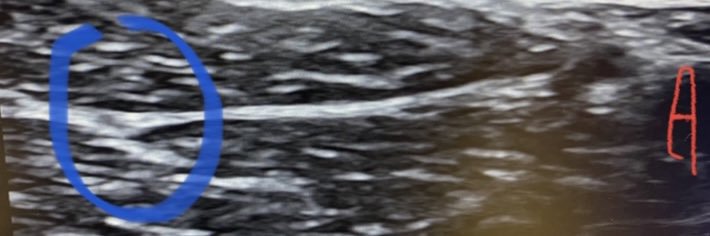

Father/son discussion at ASA 2025 MCC: Winnie Perivascular Brachial Plexus Block-An Ultrasound Revisit.